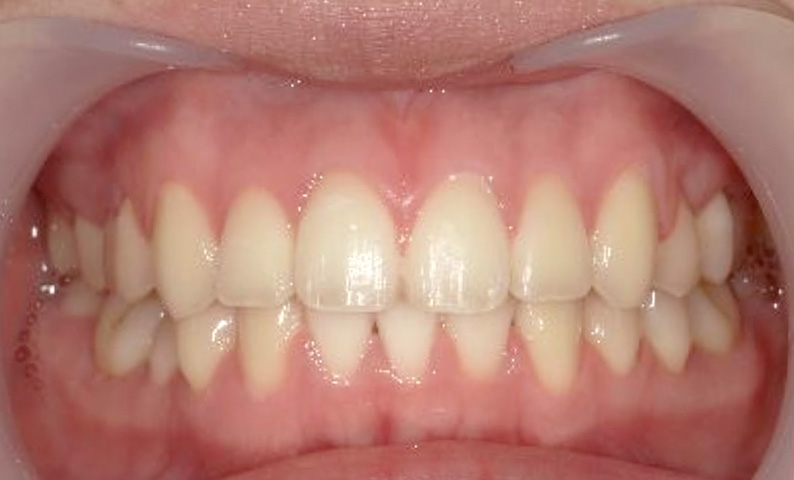

症例_022 上下顎の部分矯正

治療期間:7ヶ月金額:54万円+税女性前歯のガタガタ八重歯一部反対咬合

| Before | After |